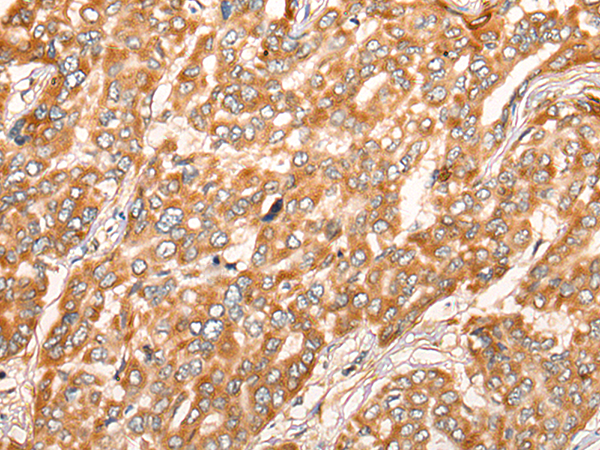

IHC positive control: |

Human liver cancer and Human thyroid cancer |